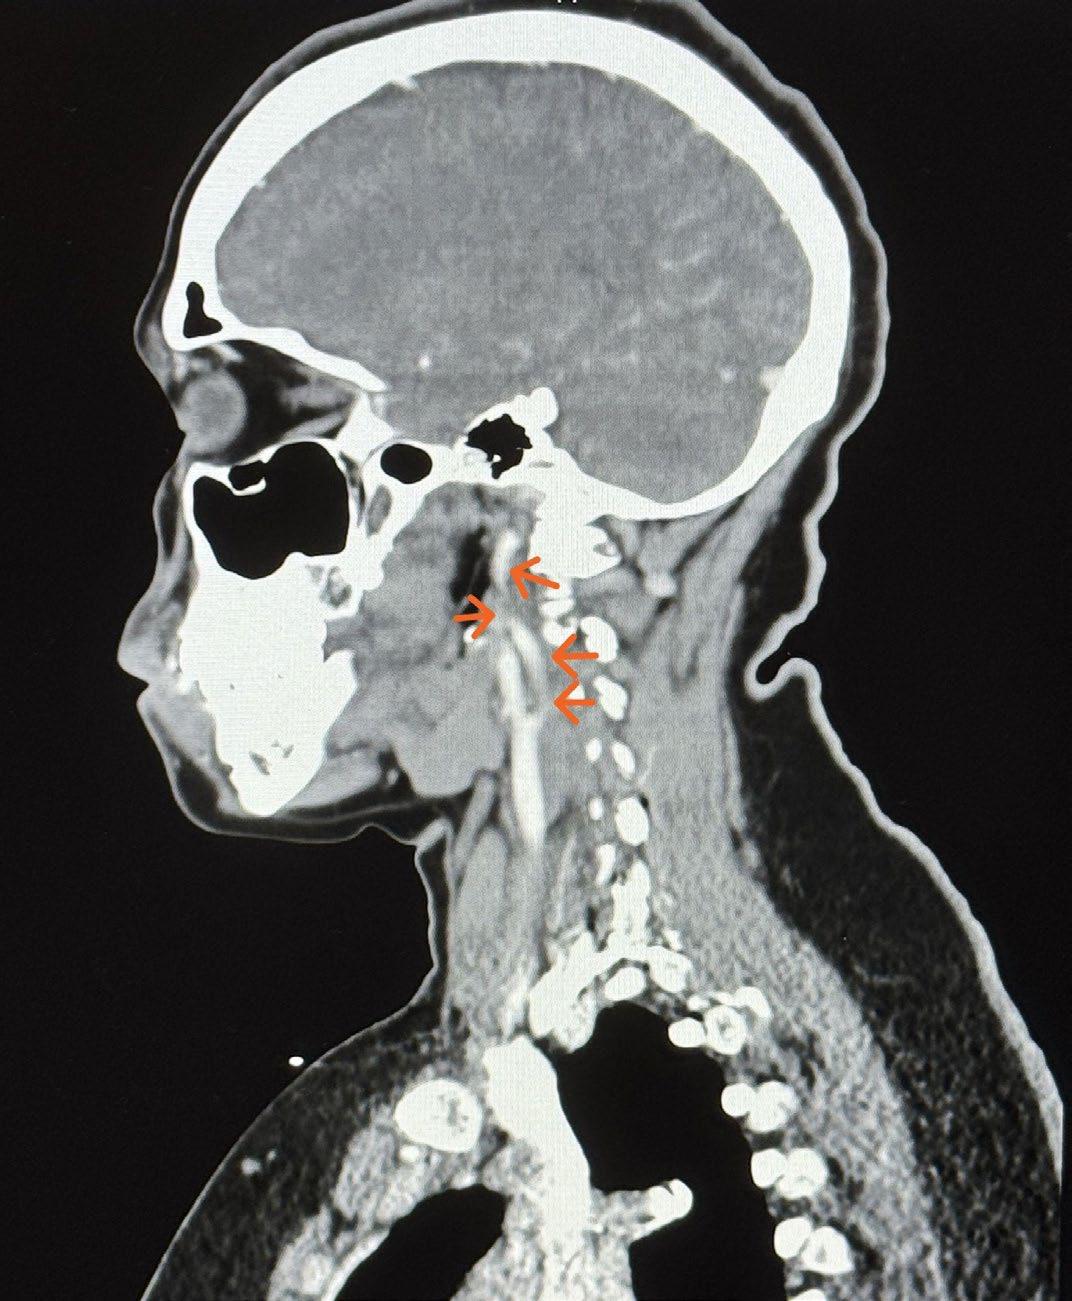

In the setting of fibromuscular dysplasia (FMD) the most common arterial involvement is the renal artery, with pathologic changes such as the “string of beads,” in 75-80% of patients. In approximately 75% of patients, the carotid and vertebral arteries are involved. Many patients present with symptoms of hypertension, headache, pulsatile tinnitus, and/or flank pain. A rare manifestation of FMD is a spontaneous dissection of the coronary artery (SCAD) [1]. SCAD is the underlying pathology in anywhere from 0.1% to 4.9% of acute coronary syndrome (ACS) [2]. However, the incidence of FMD within the group of patients diagnosed with SCAD could be as high as 86% [3]. To establish the diagnosis of FMD-associated SCAD, there must be characteristic findings of FMD on computed tomography (CT) or computed tomography angiography (CTA) in another region of the body. The classic “string of beads” appearance is often absent in coronary arteries or is inconclusive if beading was present before the dissection [3]. This appearance is caused by abnormal fibrous cells replacing normal arterial cells. Leading to areas of overly stiff and to elastic portions of the arterial wall, causing a beaded appearance.

The patient had undergone a left heart catheterization (LHC) at her previous hospitalization that showed SCAD of the LAD. She was also diagnosed with FMD of the bilateral carotid arteries via CTA of the brain/head/neck (Figure 1). Upon discharge from that hospitalization three days later, she was prescribed clopidogrel, aspirin, amlodipine, metoprolol, and sublingual nitroglycerin. She was instructed to continue taking her atorvastatin previously prescribed for hyperlipidemia following a stent placement in her LCX three years prior. It was determined that due to the previous plaqueinduced myocardial infarction, the statin should be continued. A timeline of her first hospitalization is available in Table 1, represented by the negative days. She was also instructed to follow up with outpatient cardiology for a comprehensive screening for fibromuscular dysplasia. Her second presentation to the emergency department occurred one day prior to her scheduled outpatient follow-up.